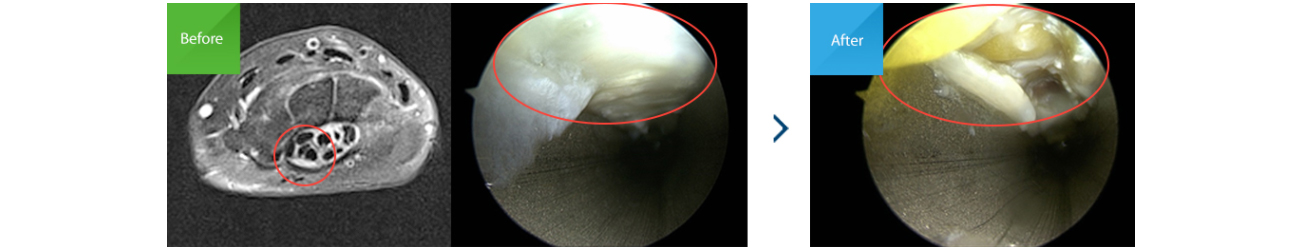

최근에는 초음파를 이용해 신경압박 정도 및 수술 후의 경과를 보기도 하며, 손목터널증후군의 원인 중 하나인 수근관 내 결절종 등 공간점유병소를

확인하기 위해 MRI를 이용하는 경우도 있습니다.

보존적 치료에 반응하지 않는 경우, 증상이 심하거나 10개월 이상 지속된 경우, 지속적인 무감각과 근위축이 있는 경우 등에서 고려할 수 있습니다.

만약 수술적 치료가 필요한 시기에 방치할 경우, 정중신경의 허혈(혈류가 부족한 상태)이 진행되어 신경자체의 섬유화 등 2차 변화가 오게 되면

수술 후에도 좋은 결과를 기대하기 어려울 수도 있습니다.

기존의 전통적인 방법으로 3cm 정도 절개를 통해 횡수근 인대를 절제하는 수술입니다.